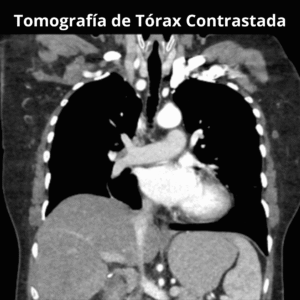

Tomografía Multicorte

Ponemos a tu disposición nuestro servicio de Tomografía Multicorte, este tipo de estudio utiliza rayos x para obtener imágenes detalladas del interior de tu cuerpo. La imagen muestra los huesos, órganos y tejidos blandos con mayor claridad que las radiografías convencionales.

> Tórax

Simple

Contrastada*